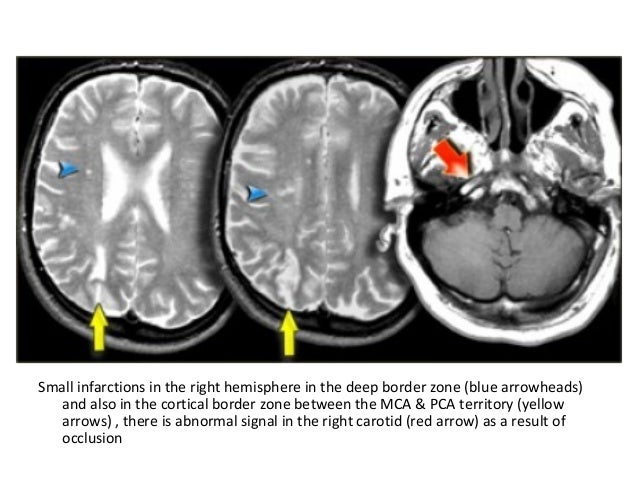

Border Zone Infarcts Pathophysiologic And Imaging Characteristics Radiographics

The Radiology Assistant Vascular Territories

radiologyassistant.nl